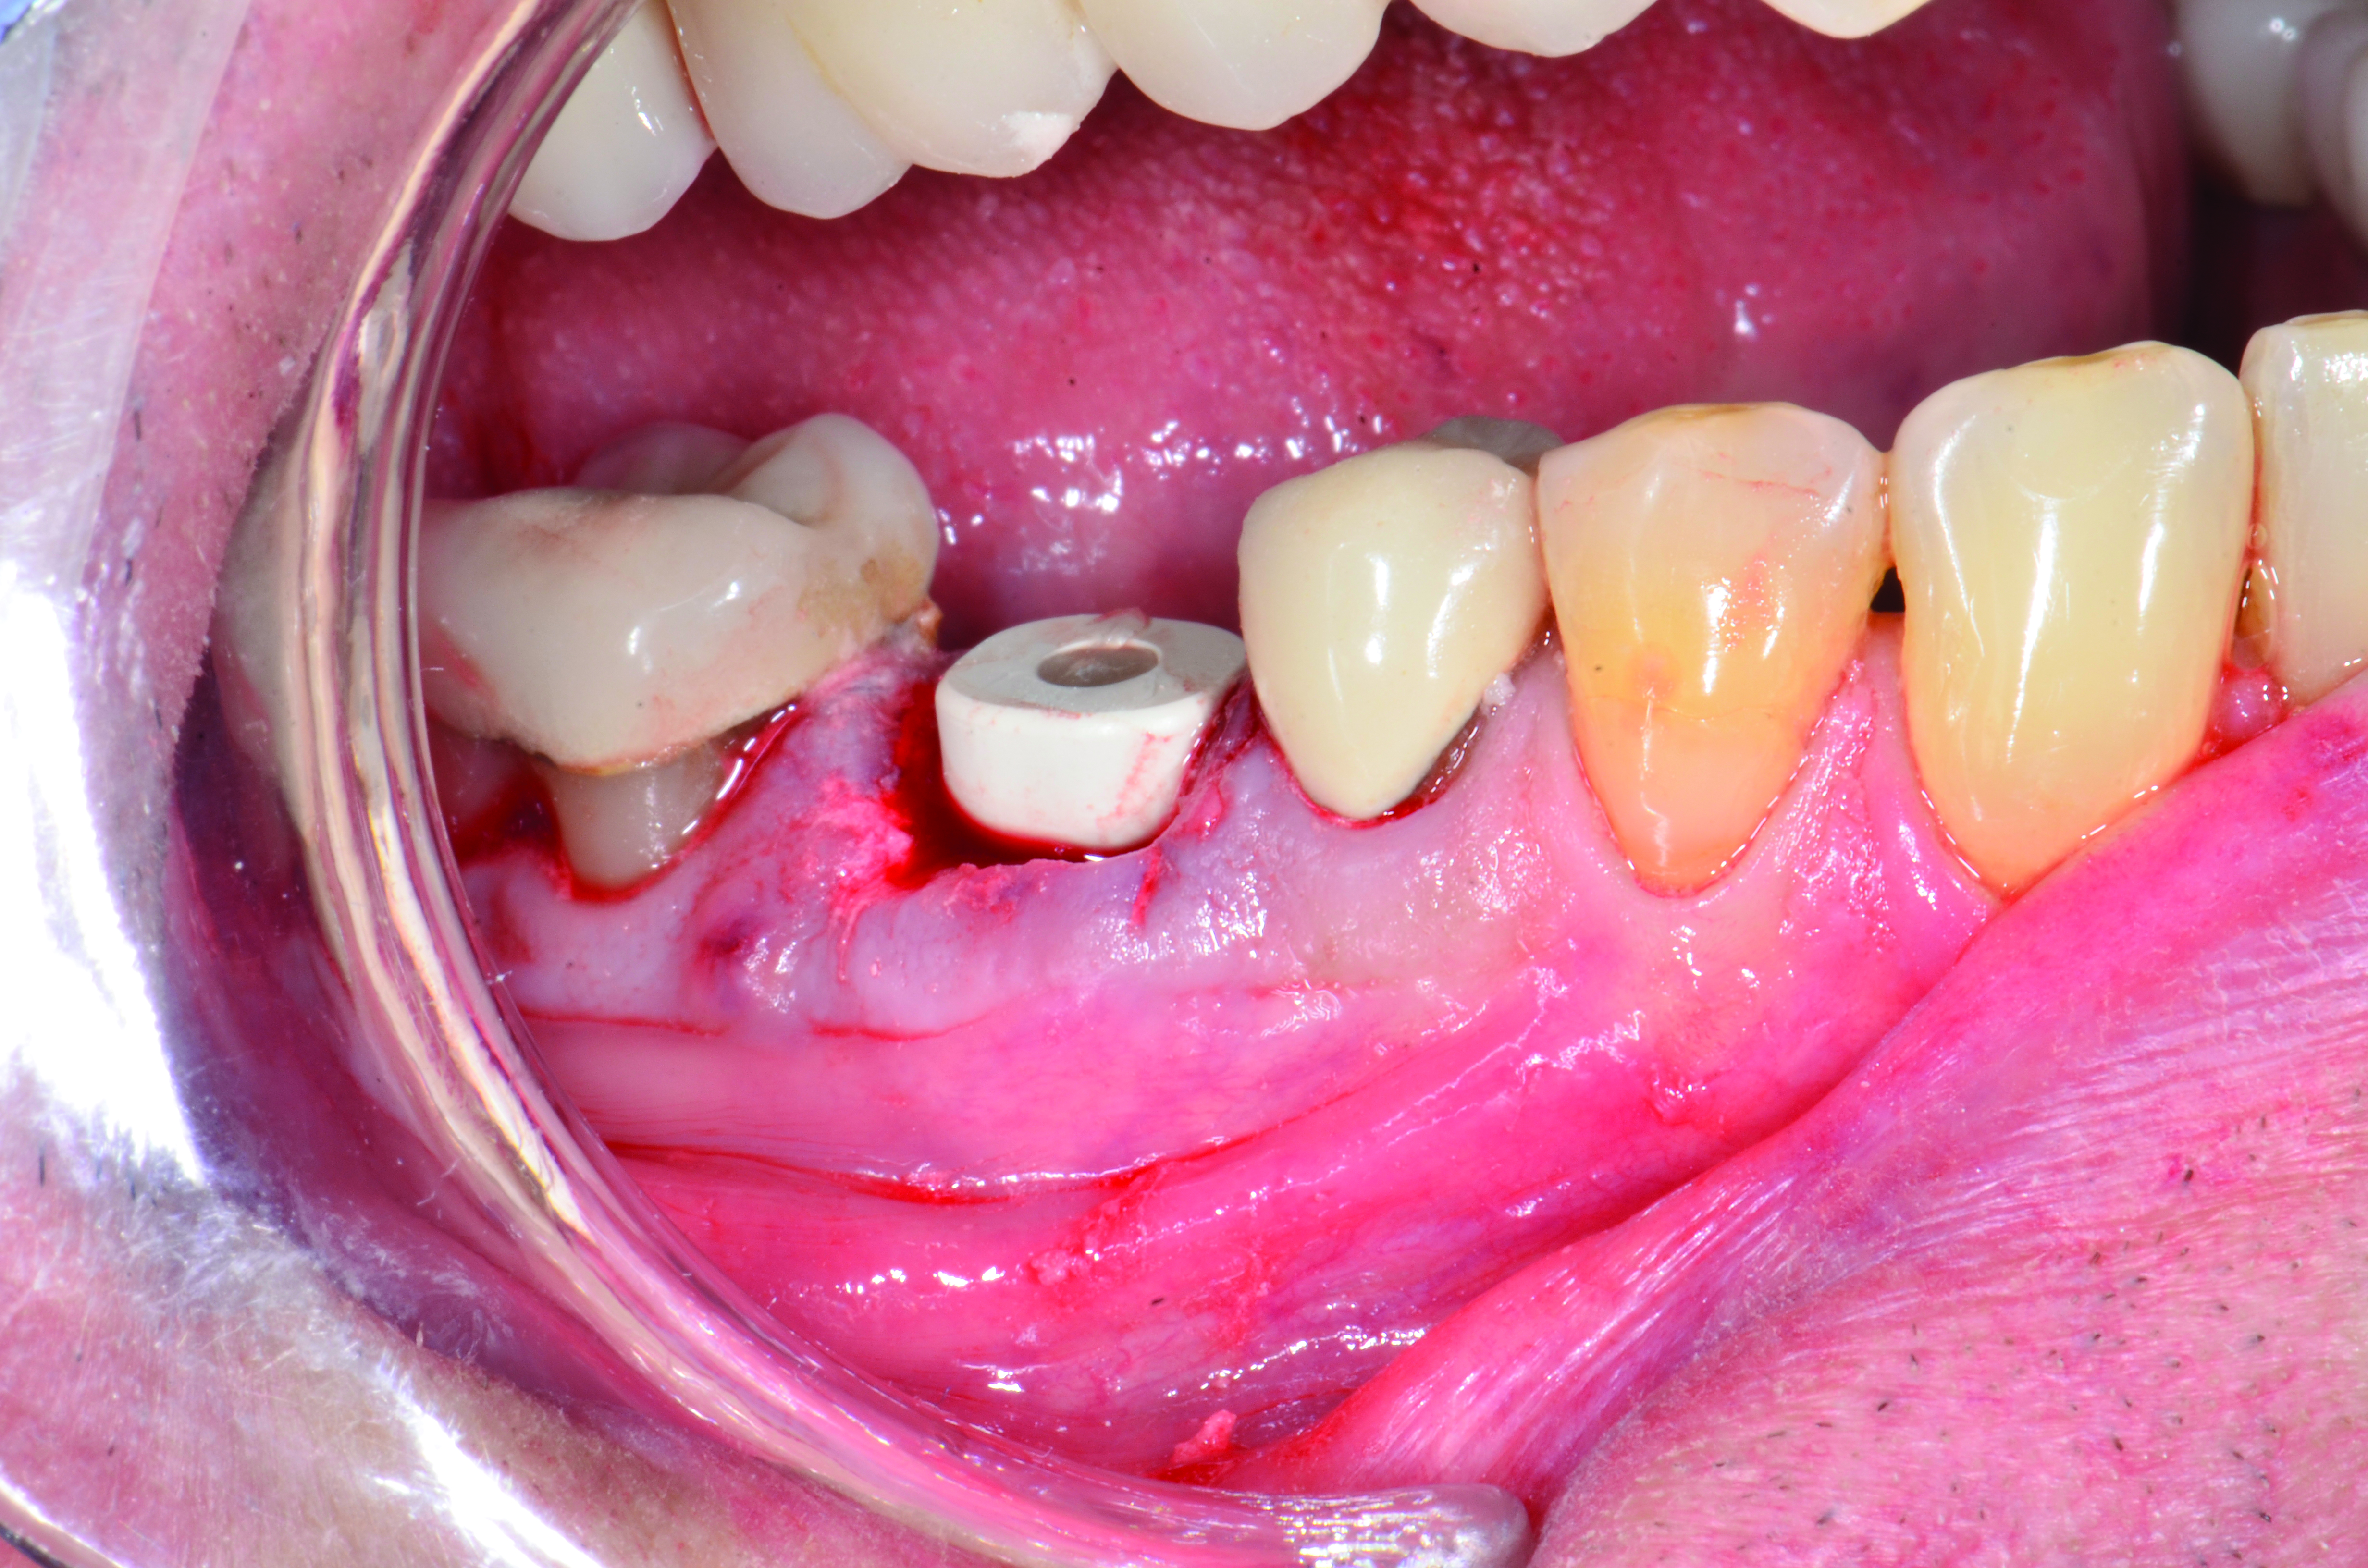

A mandibular right first molar was extracted due to an advanced Class III furcation and an irreversible pulpitis—a combination lesion. An immediate implant placement protocol was elected, and a PEEK abutment was placed on the implant (Figure 1). After 3 months of healing, a scan body was placed on the osseointegrated implant (Figure 2 and Figure 3), and an intraoral scan was taken (TRIOS Pod) (Figure 4) for the fabrication of a screw-retained crown.

Once the STL file generated from the intraoral scanner was sent to the laboratory (Figure 5), the technician used proprietary software to design the crown (Figure 6 through Figure 8), mill the crown, and digitally print a SLA model (Dental SG, Formlabs, www.formlabs.com) (Figure 9 through Figure 11), and then finish the crown on the digitally printed model. The angulated screw-channel full-zirconia crown (Nobel Biocare) (Figure 12) was seated, and contacts were evaluated intraorally and adjusted extraorally. The screw-retained crown was torqued to 35 Ncm2, and the screw access was sealed (Figure 13 through Figure 15).

Fig 15. Final restoration of mandibular right first molar.

Figure 15